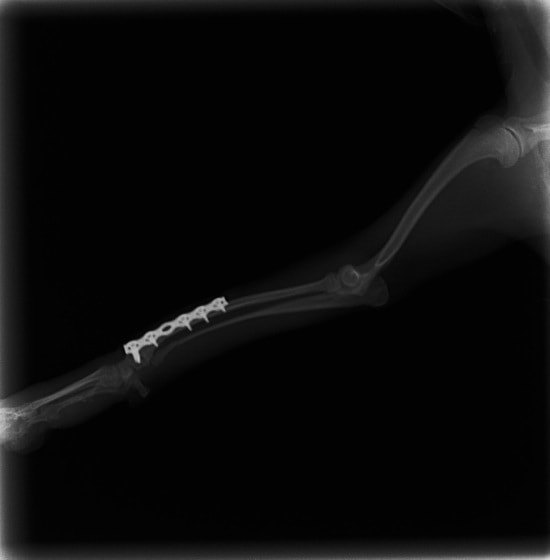

ペルシャ猫 11ヶ月齢 雄

他院にて左大腿骨遠位の成長板骨折(salter-harrisⅠ型)が認められており、治療相談を目的として来院。当院にて、キルシュナーワイヤーを用いたピンニングにより骨折部位の整復を行いました。術後の経過は良好で、現在も経過観察中です。

術後レントゲン

Arthrex社のターゲティングデバイスを用いてピンニングの位置を調整することで、確実な固定を行っています。当院ではこの手術器具以外にも、人の手術にも使用される様々な器具を導入し、手術精度を高め、また医療メーカーと新しい器具の開発、試作にも取り組んでおります。